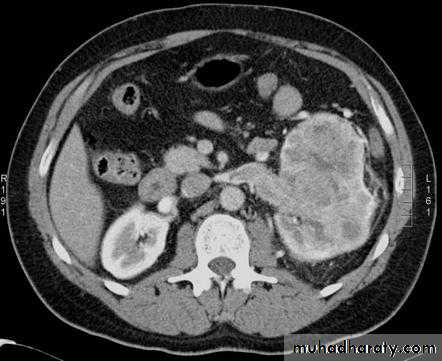

Renal cell carcinomas

Spherical and often lobulated, usually isodense to renal parenchyma.Focal necrotic areas may result in areas of low density, and stippled calcification may be present in the interior of the mass.

Renal cell carcinomas enhance, but not to the same degree as the normal renal parenchyma. The enhancement is inhomogeneous.

Check LN, liver, adrenal, pancreas, bone, renal vein and IVC